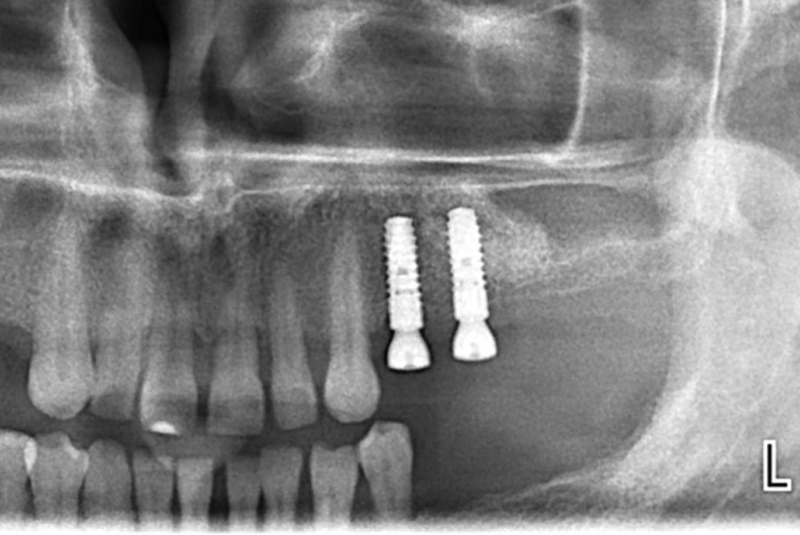

- IMPLANTÁT - je náhrada strateného zuba a používa sa pri strate jedného alebo viacerých zubov, prípadne pri celkovej rekonštrukcii bezzubej čeľuste alebo sánky. Ide o progresívnu metódu, pri ktorej sa zavádza titánová “skrutka” do kosti čeľuste alebo sánky. Implantát tak zastupuje funkciu pôvodného koreňa zuba. V ďalšom kroku sa zhotoví protetická náhrada (korunka, mostík, snímateľná náhrada). Podmienkou pre zavedenie dentálneho implantátu je dostatočná kvalita kosti, ústna dutina bez známok zápalu, či bez zubného kazu a samozrejme dokonalá ústna hygiena.

Sólo korunky, nahradené implantátmi